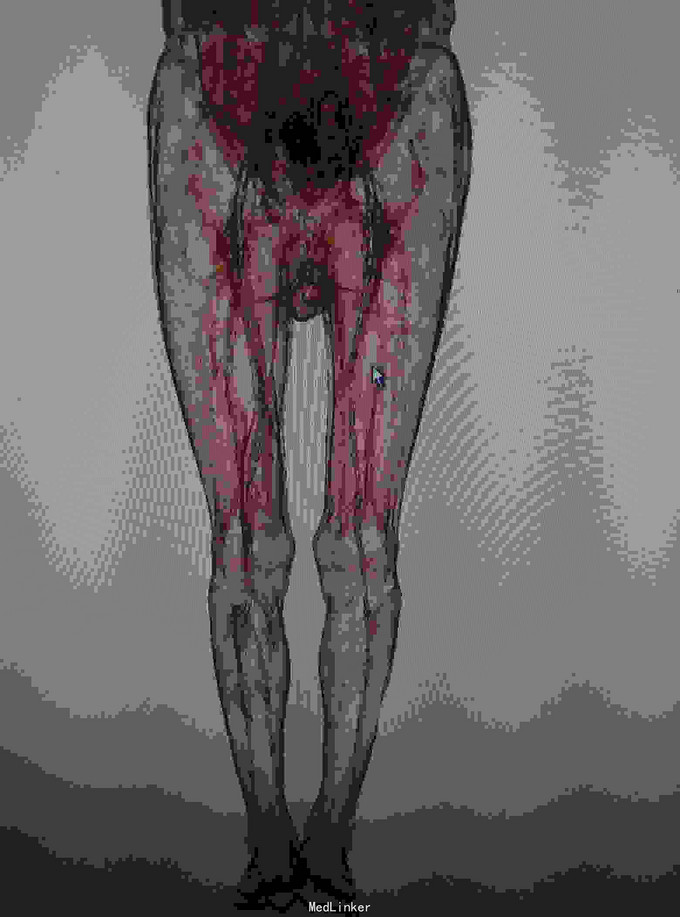

左下肢皮温降低,左足背可见紫红色淤斑,左股动脉扪及微弱波动。下肢血管成像提示:双下肢动脉节段性不同程度狭窄、闭塞。

双下肢动脉硬化闭塞症 手术:左侧髂动脉探查术,术中探查股动脉,导丝导管尝试通过闭塞段髂动脉,但反复尝试无法继续。右侧也无法通过。家属放弃。